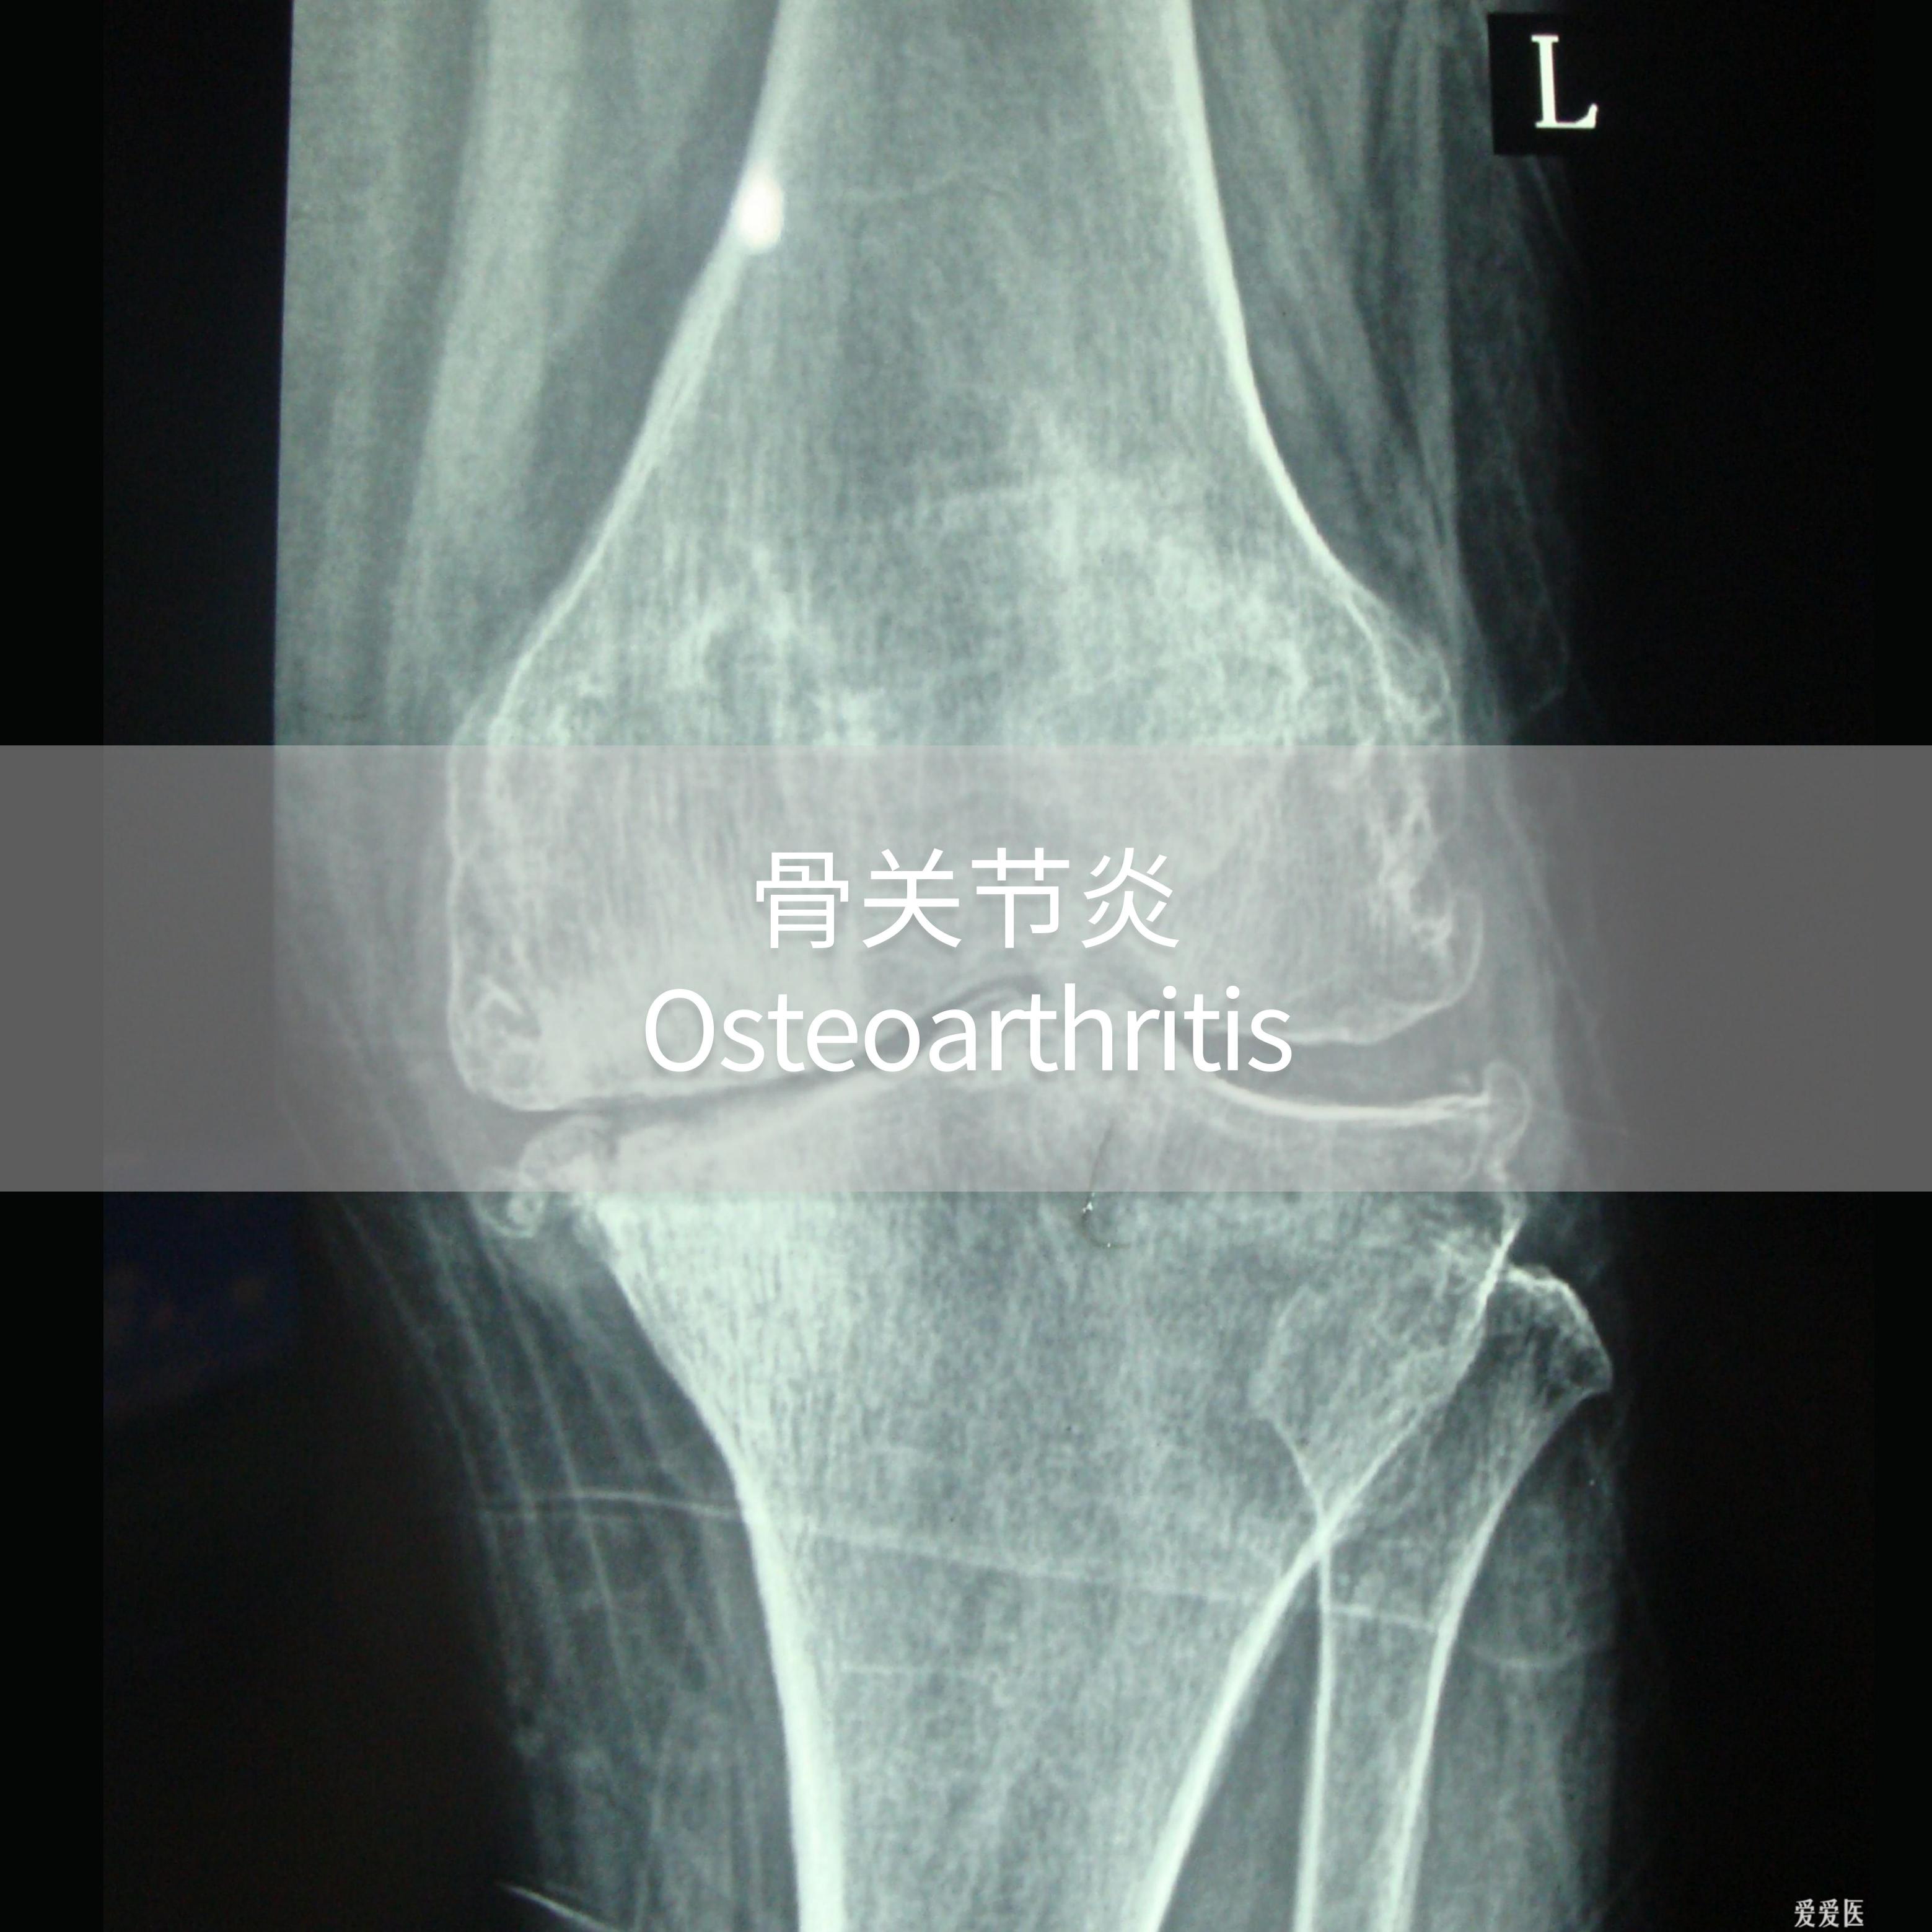

Bone & joint health

Rabpharma is dedicated to the research and development of first-in-class new drugs in the field of bone and joint diseases.